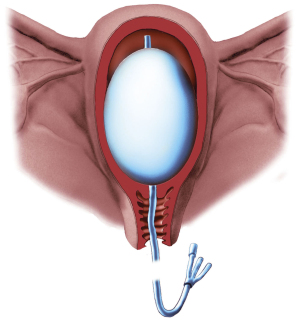

Intervenční radiologie